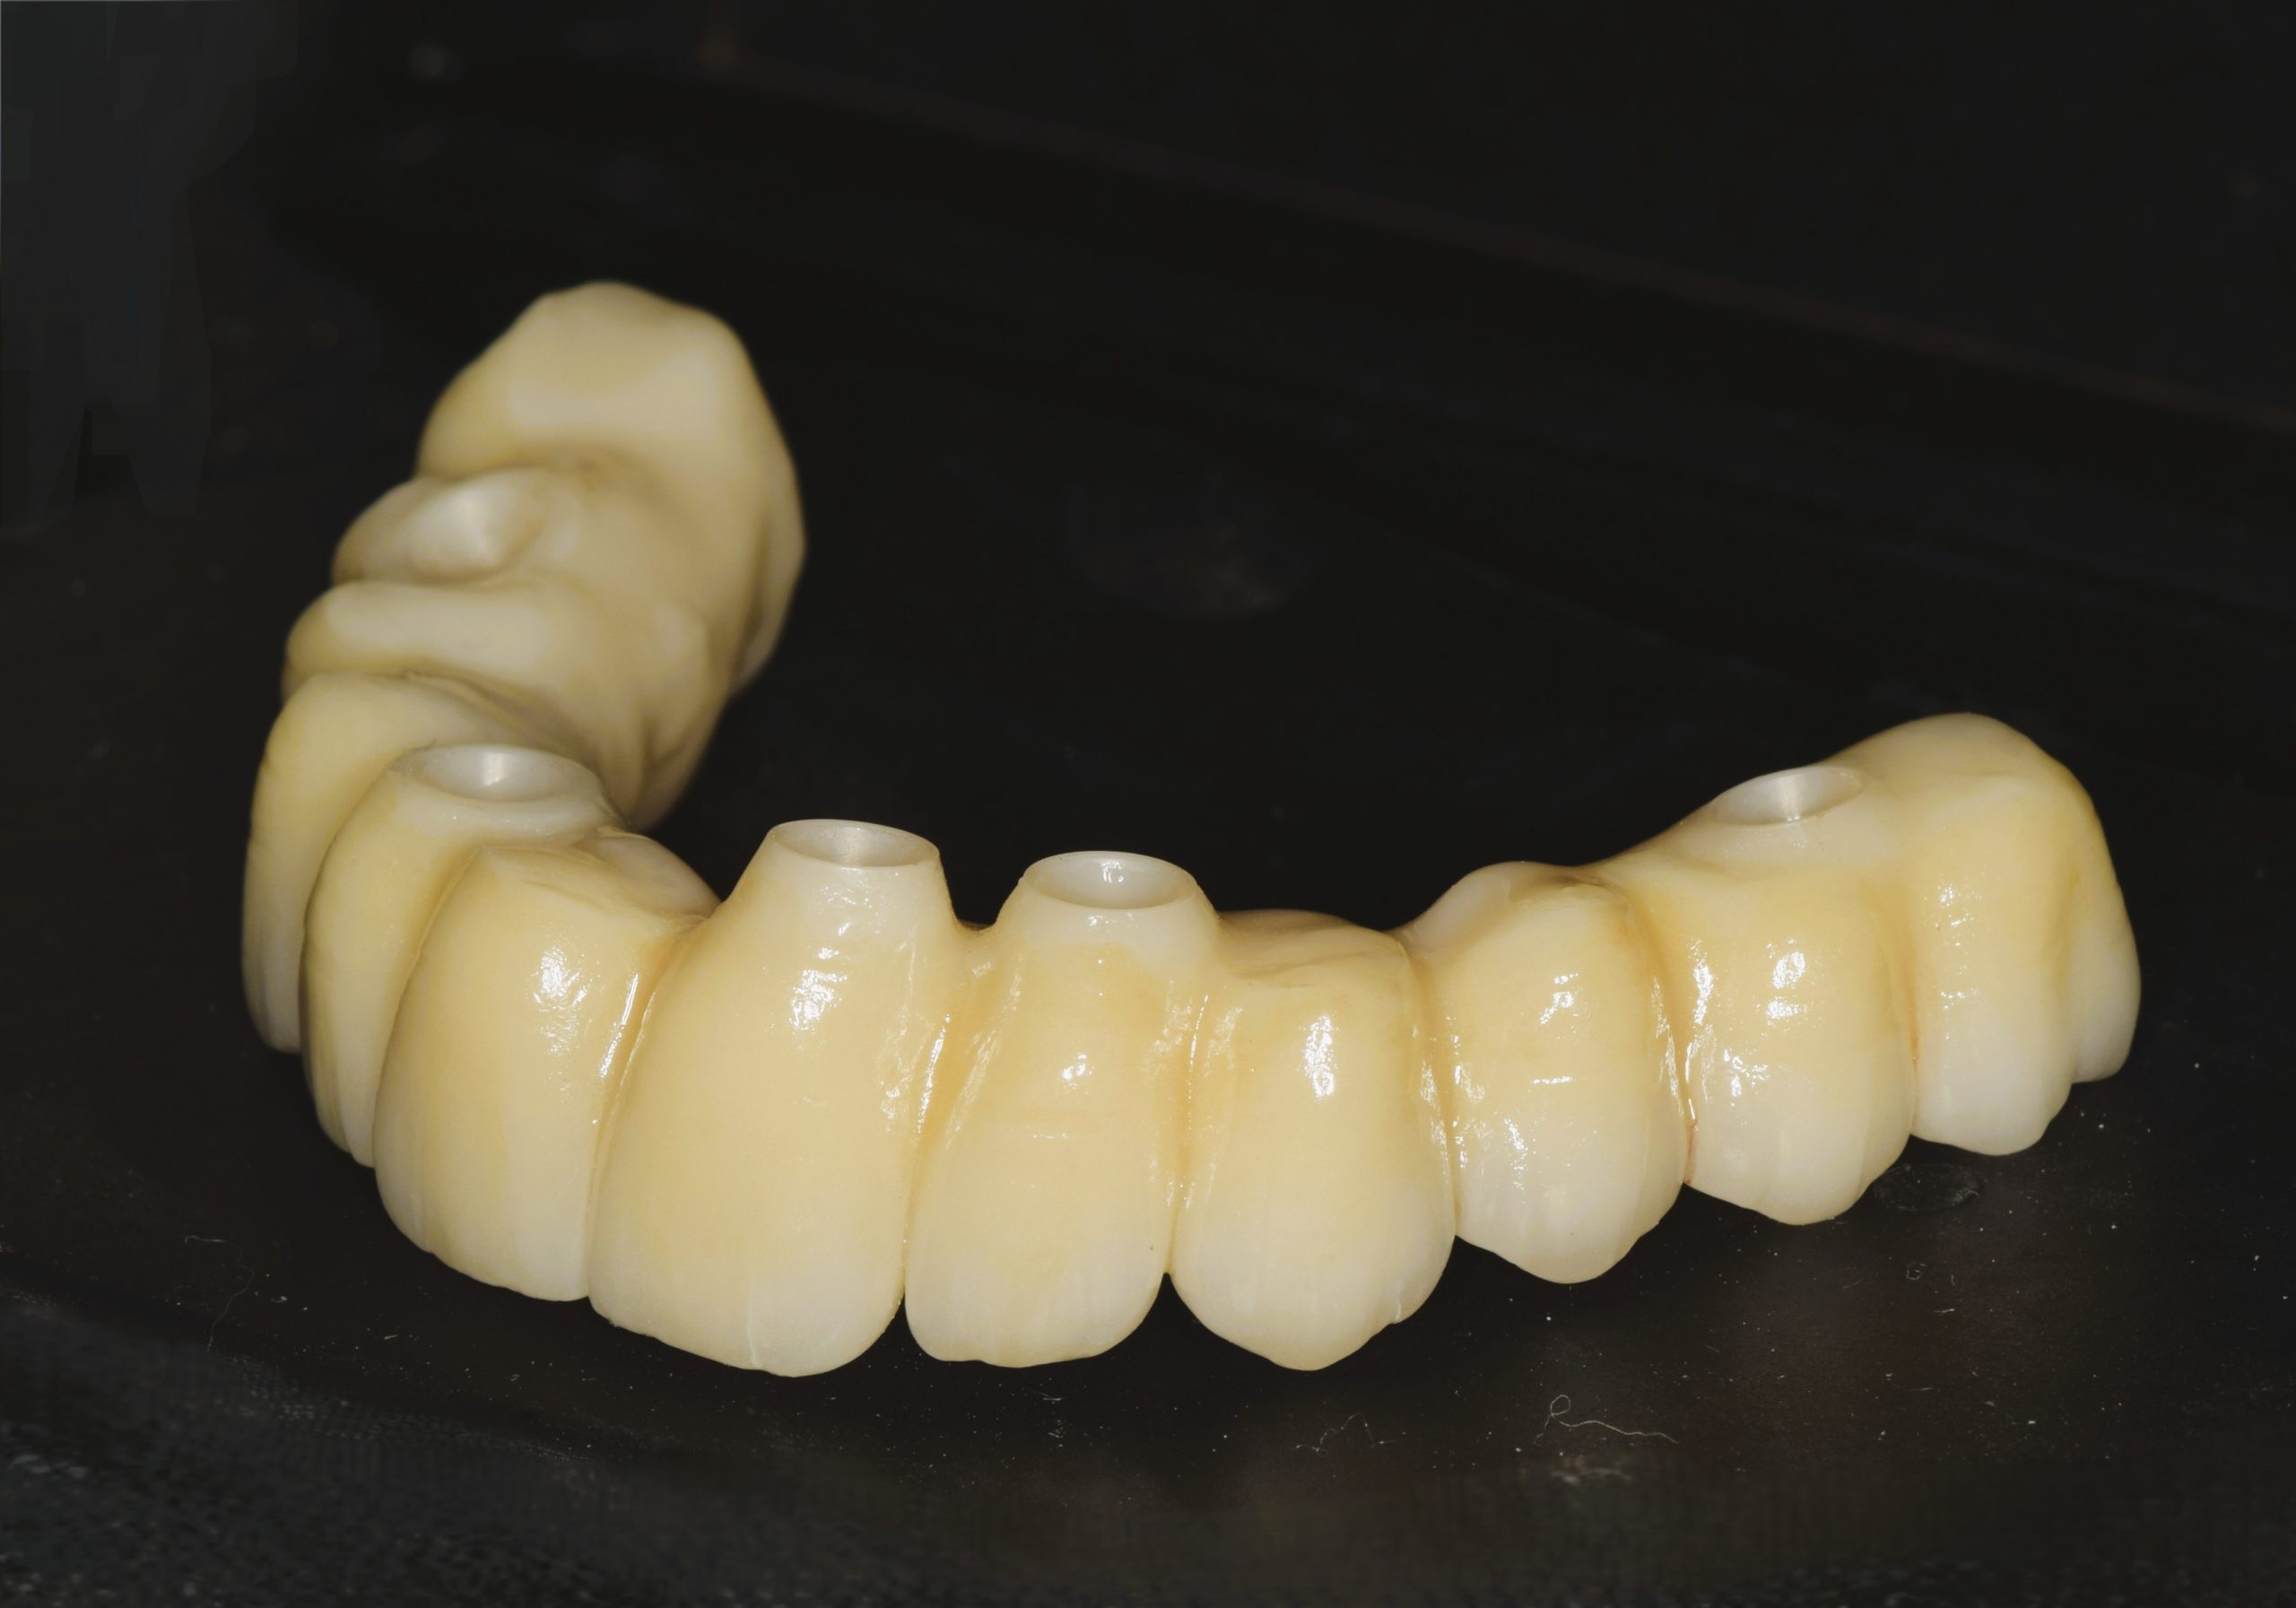

Module III – Indications des différentes conceptions

- Choix du pilier prothétique et espace biologique

- Choix de l’infrastructure

- Choix des matériaux cosmétiques, communication, teinte

- Prothèse vissée ou scellée ? Spécificités